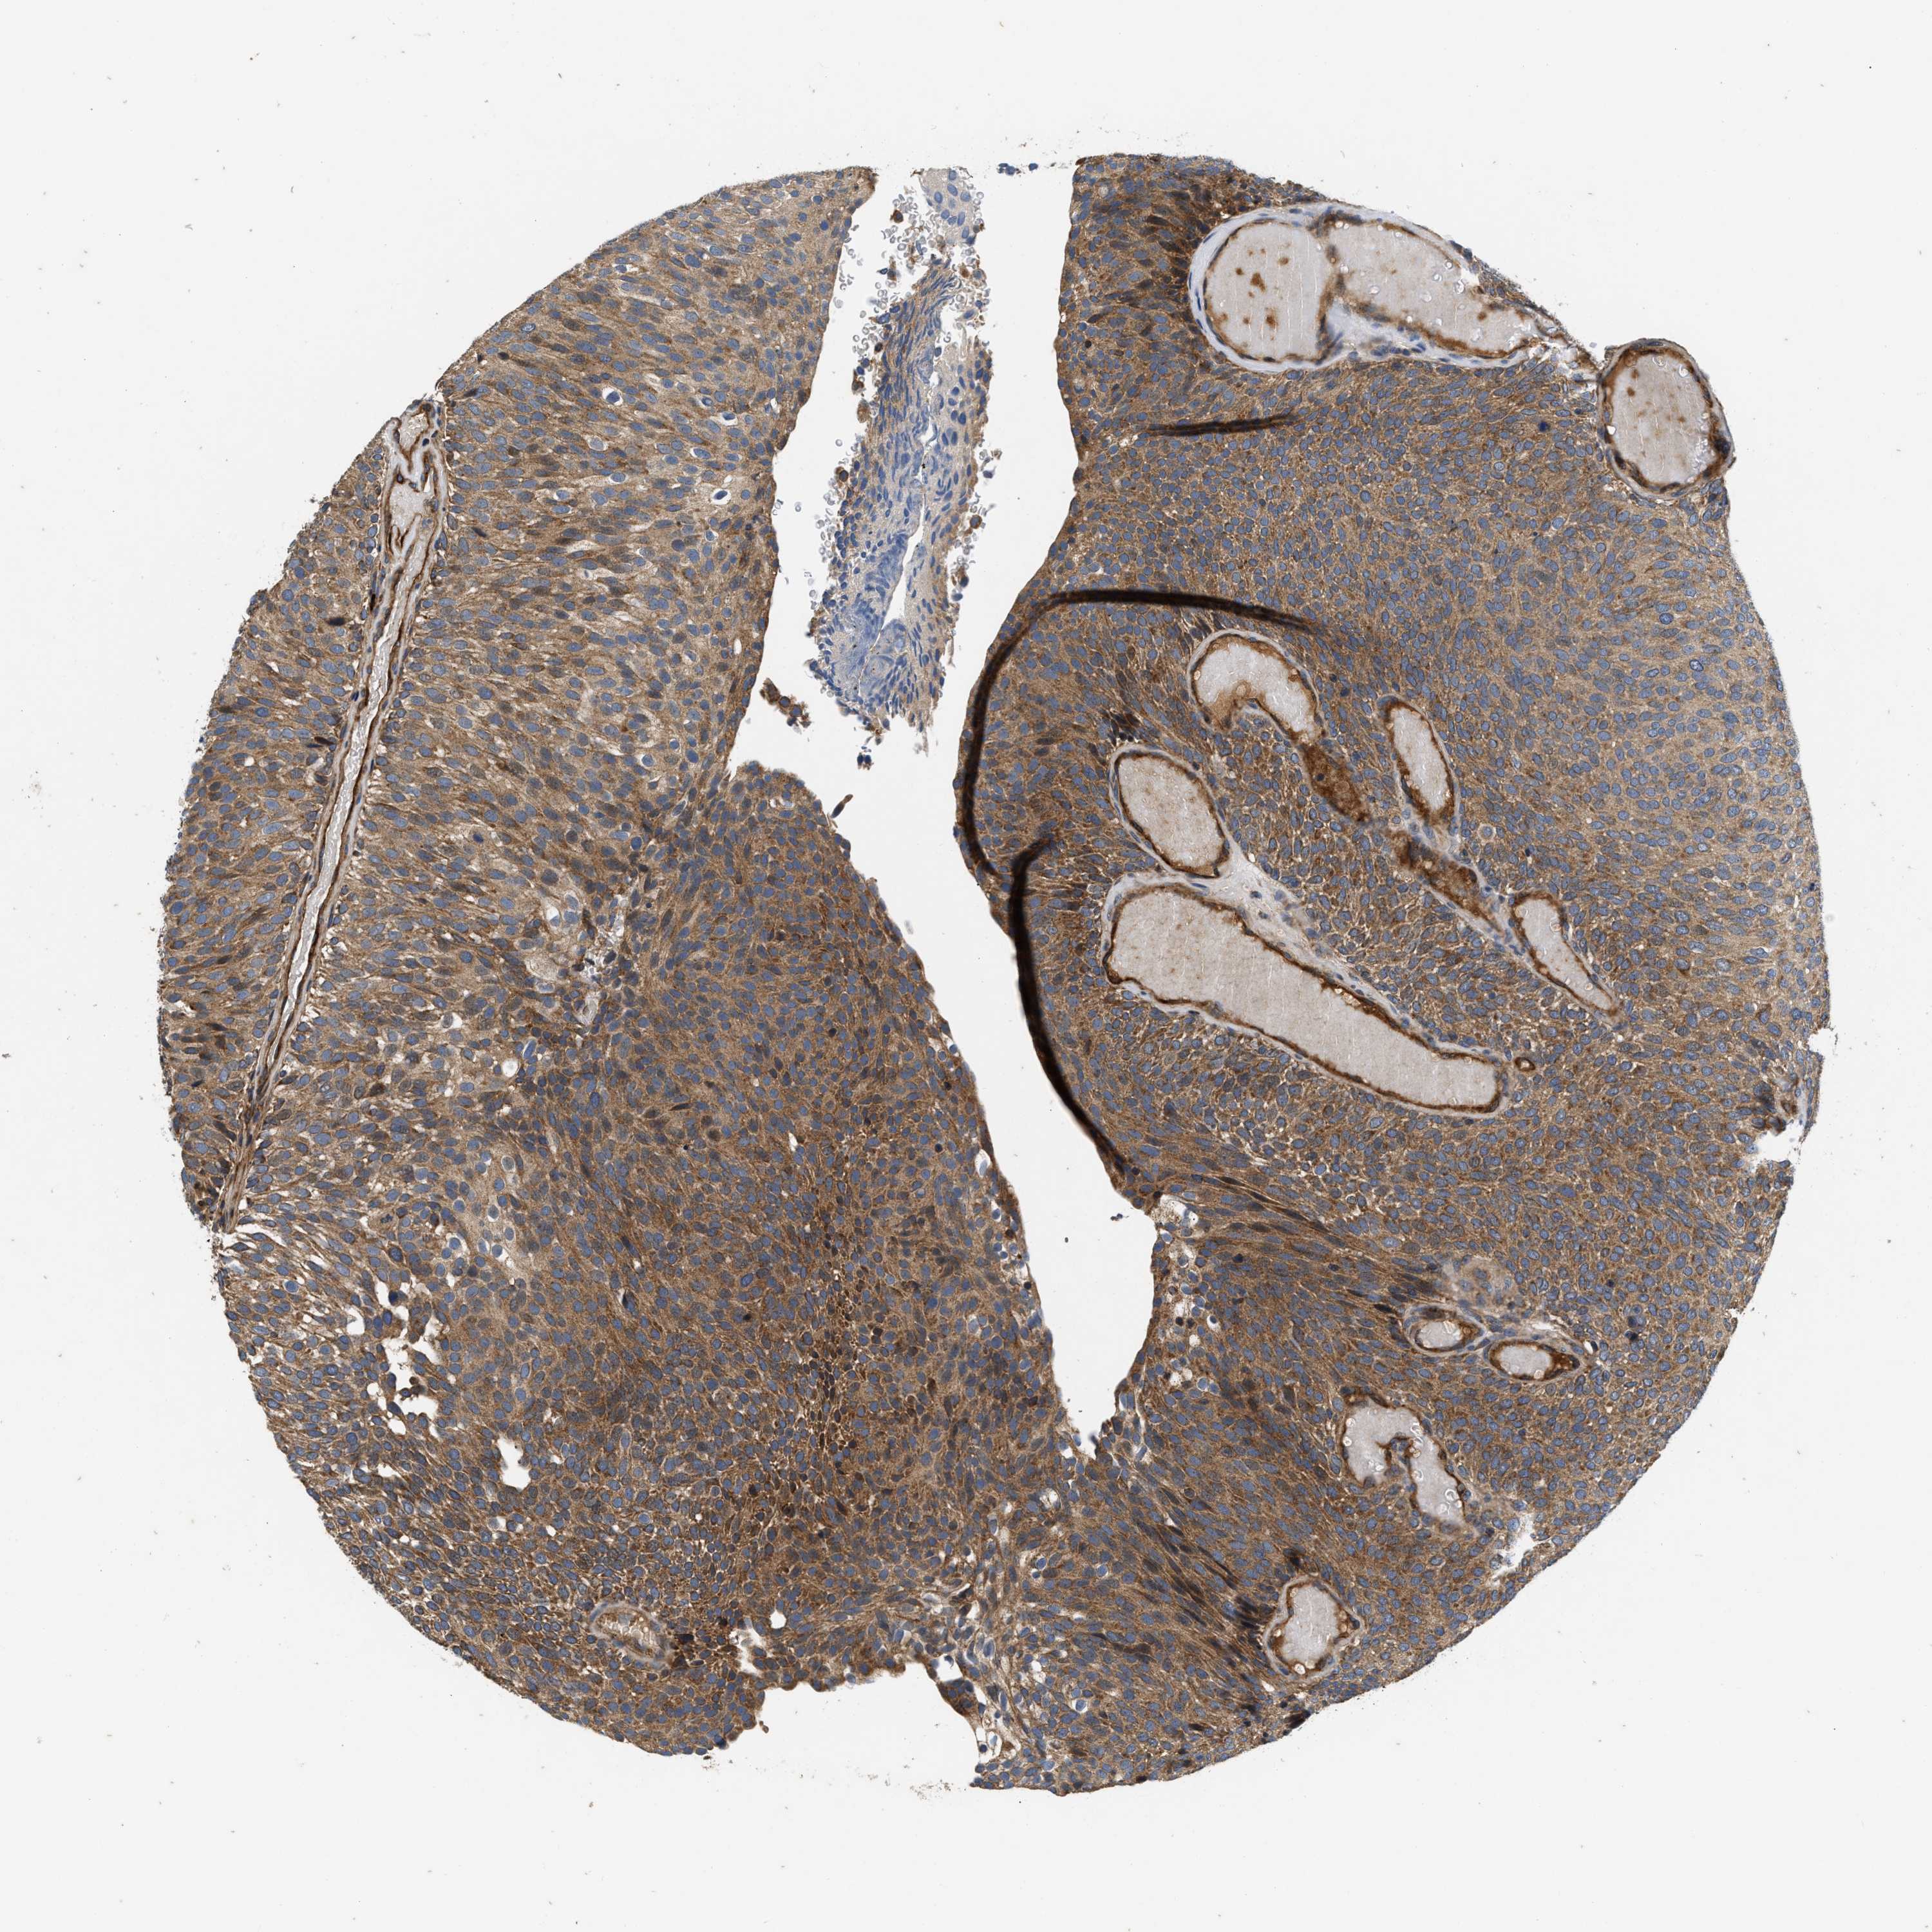

UROTHELIAL CANCER - Protein expressioni

A mouse-over function shows sample information and annotation data. Click on an image to view it in a full screen mode. Samples can be filtered based on level of antibody staining by selecting one or several of the following categories: high, medium, low and not detected. The assay and annotation is described here.

Antibody stainingi

Antibody staining in the annotated cell types in the current human tissue is reported as not detected, low, medium, or high, based on conventional immunohistochemistry profiling in selected tissues. This score is based on the combination of the staining intensity and fraction of stained cells.

Each image is clickable and will lead to virtual microscopy that enables deeper exploration of all samples and also displays staining intensity scores, fraction scores and subcellular localization as well as patient and tissue information for each sample.

Antibody HPA017909

Staining

High

Medium

Low

Not detected

Intensity

Strong

Moderate

Weak

Negative

Quantity

>75%

75%-25%

<25%

None

Location

Nuclear

Cytoplasmic/membranous

Cytoplasmic/membranous,nuclear

Urothelial carcinoma, Low grade

Urothelial carcinoma, High grade